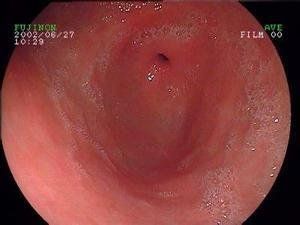

1.胃鏡檢查胃黏膜病理活檢是診斷手術後反流性胃炎最重要的診斷步驟。手術後反流性胃炎胃鏡表現胃體或殘胃黏膜紅色、充血水腫、組織脆弱、接觸容易出血、散發淺表潰瘍、胃鏡下可以見到黏膜下血管襻。

胃鏡觀察下,有膽汁反流者均有不同程度的淺表性及/或萎縮性胃炎。淺表性胃炎病變黏膜有程度不等的充血、水腫、粘液斑等改變;萎縮性胃炎所見黏膜呈灰白色,致黏膜紅白相間,可伴有腸上皮化生。部分病例有結節形成,黏膜變薄透見血管,少數見黏膜糜爛和潰瘍形成。